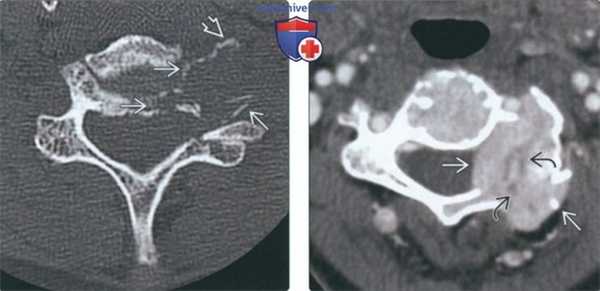

(Слева) Аксиальный КТ- срез: множественные округлые узелки склероза в теле нижнегрудного позвонка, представляющие собой бластические метастазы рака молочной железы.

(Справа) На Т1-ВИ у этой же пациентки определяются бластические метастатические поражения, имеющие форму округлых узелков очень низкой интенсивности в телах грудных и поясничных позвонков.